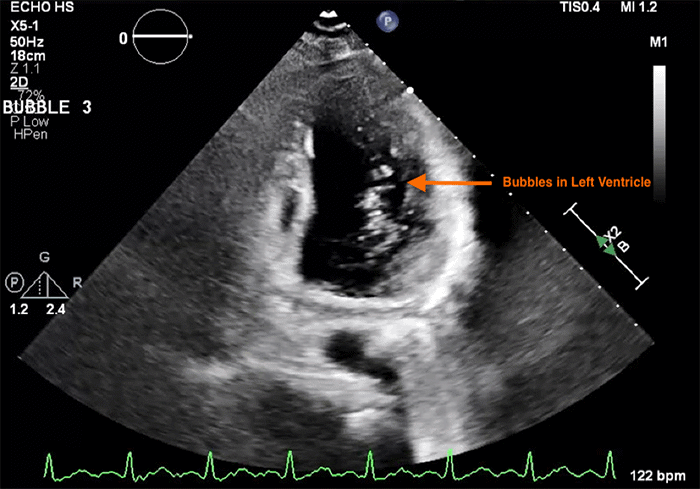

The secondary survey was notable for abrasions to the forehead and anterior chest, in addition to a fractured left fifth digit. A chest radiograph was unremarkable. Radiographs of the lower extremities confirmed bilateral displaced femoral shaft fractures (Figure 1). Bilateral Hare traction was applied, and the patient proceeded to a trauma pan-computed tomography (CT) scan. CT imaging of the head, cervical spine, and chest showed no acute traumatic abnormalities. However, the CT scan of the abdomen and pelvis incidentally revealed real-time fat emboli (density approximately -100 Hounsfield units) in transit within the bilateral femoral veins (Figure 2); this study was otherwise negative for acute intra-abdominal or pelvic trauma.

Figure 2. CT Demonstrating Bilateral Femoral Vein Fat Emboli. Published with Permission

CT of the abdomen and pelvis. (A) Axial view and (B) Sagittal reformatted view. Both images reveal low-attenuation material (approximately -100 Hounsfield units, arrows) within the bilateral femoral veins, forming distinct blood-fat levels. These findings are consistent with fat emboli in transit